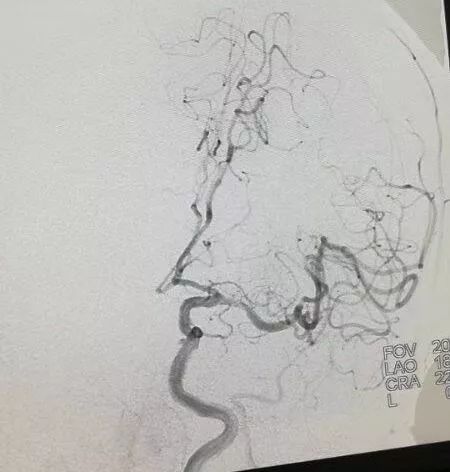

靜脈溶栓治療后,患者血管未能開通,經(jīng)與家屬溝通,張騏主任決定對(duì)患者行緊急全腦血管造影+機(jī)械取栓。神經(jīng)內(nèi)科卒中小組當(dāng)即會(huì)同神經(jīng)外科、介入科、麻醉科、影像科、導(dǎo)管室等相關(guān)科室組成的搶救團(tuán)隊(duì)共同為患者行機(jī)械取栓治療。造影顯示患者右側(cè)頸內(nèi)動(dòng)脈起始段和右側(cè)頸外動(dòng)脈起始段均閉塞,搶救團(tuán)隊(duì)密切配合,熟練的將取栓支架置入血管取出栓塞斑塊,兩次取栓先后順利完成,造影顯示動(dòng)脈已順利開通。